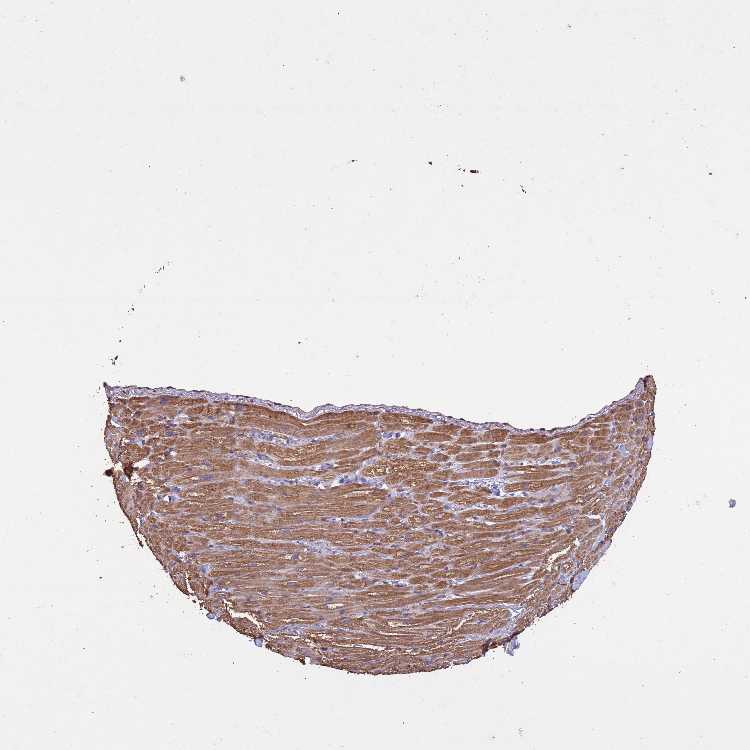

HEART MUSCLE - Antibody stainingi

Antibody staining in the annotated cell types in the current human tissue is reported as not detected, low, medium, or high, based on conventional immunohistochemistry profiling in selected tissues. This score is based on the combination of the staining intensity and fraction of stained cells.

Each image is clickable and will lead to virtual microscopy that enables deeper exploration of all samples and also displays staining intensity scores, fraction scores and subcellular localization as well as patient and tissue information for each sample.

Antibody HPA047858

Cardiomyocytes Medium